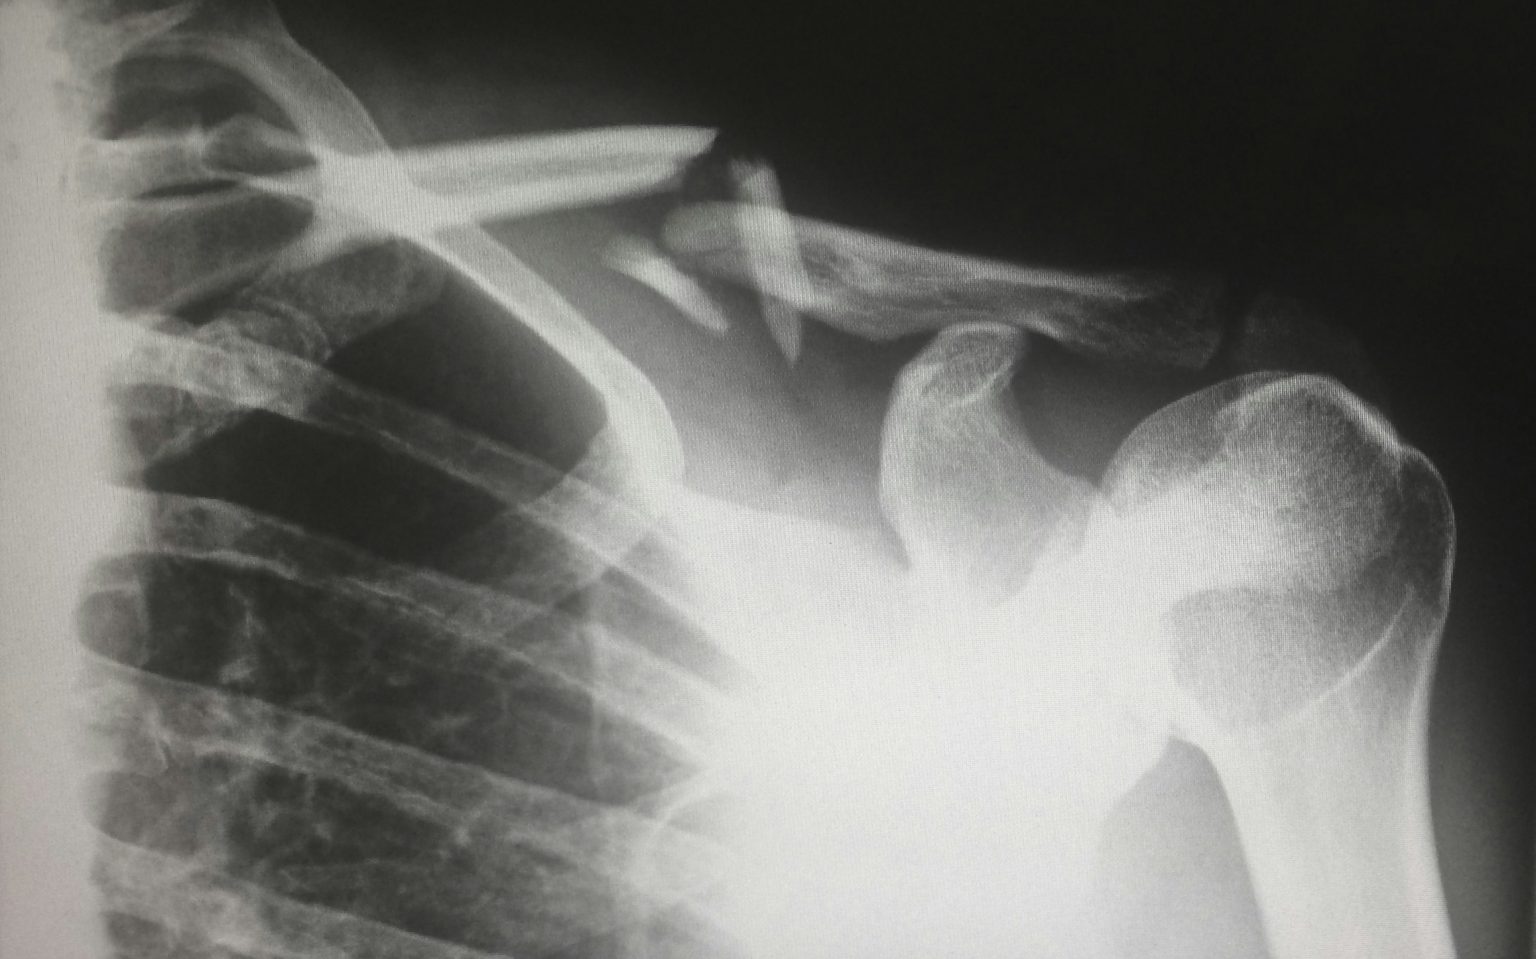

Many people experience shoulder pain at some point in their lives, but not all pain requires surgery. In some cases, however, the damage is too significant to heal on its own. Common conditions that may lead to surgical intervention include rotator cuff tears, shoulder impingement, dislocation, frozen shoulder, labral tears, arthritis, and fractures. These issues can be caused by aging, sports injuries, accidents, or degenerative diseases.

For more severe cases, open surgery or joint replacement may be necessary. Total shoulder replacement involves replacing the damaged parts of the shoulder joint with artificial components, helping to relieve pain and restore motion. Reverse shoulder replacement, which reverses the normal ball-and-socket mechanics, is often used for patients with completely torn rotator cuffs and severe arthritis.